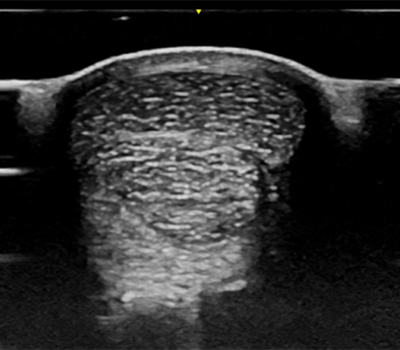

Ultrasound

Bay Equine veterinarians utilise the latest ultrasound technology to image the musculoskeletal system, thorax and abdomen of your horse. This allows helps us to get to the cause of your horses problems quickly.